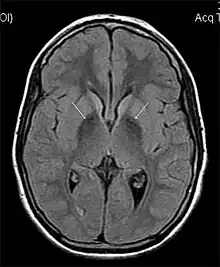

MRI hypointensity (white arrows) in the globus pallidi that indicates the presence of iron deficiencies which would be seen in a diagnosis of Aceruloplasminemia

Diagnosis of this disorder depends on blood tests demonstrating the absence of serum ceruloplasmin, combined with low serum copper concentration, low serum iron concentration, high serum ferritin concentration, or increased hepatic iron concentration. MRI scans can also confirm a diagnosis; abnormal low intensities can indicate iron accumulation in the brain.[5]